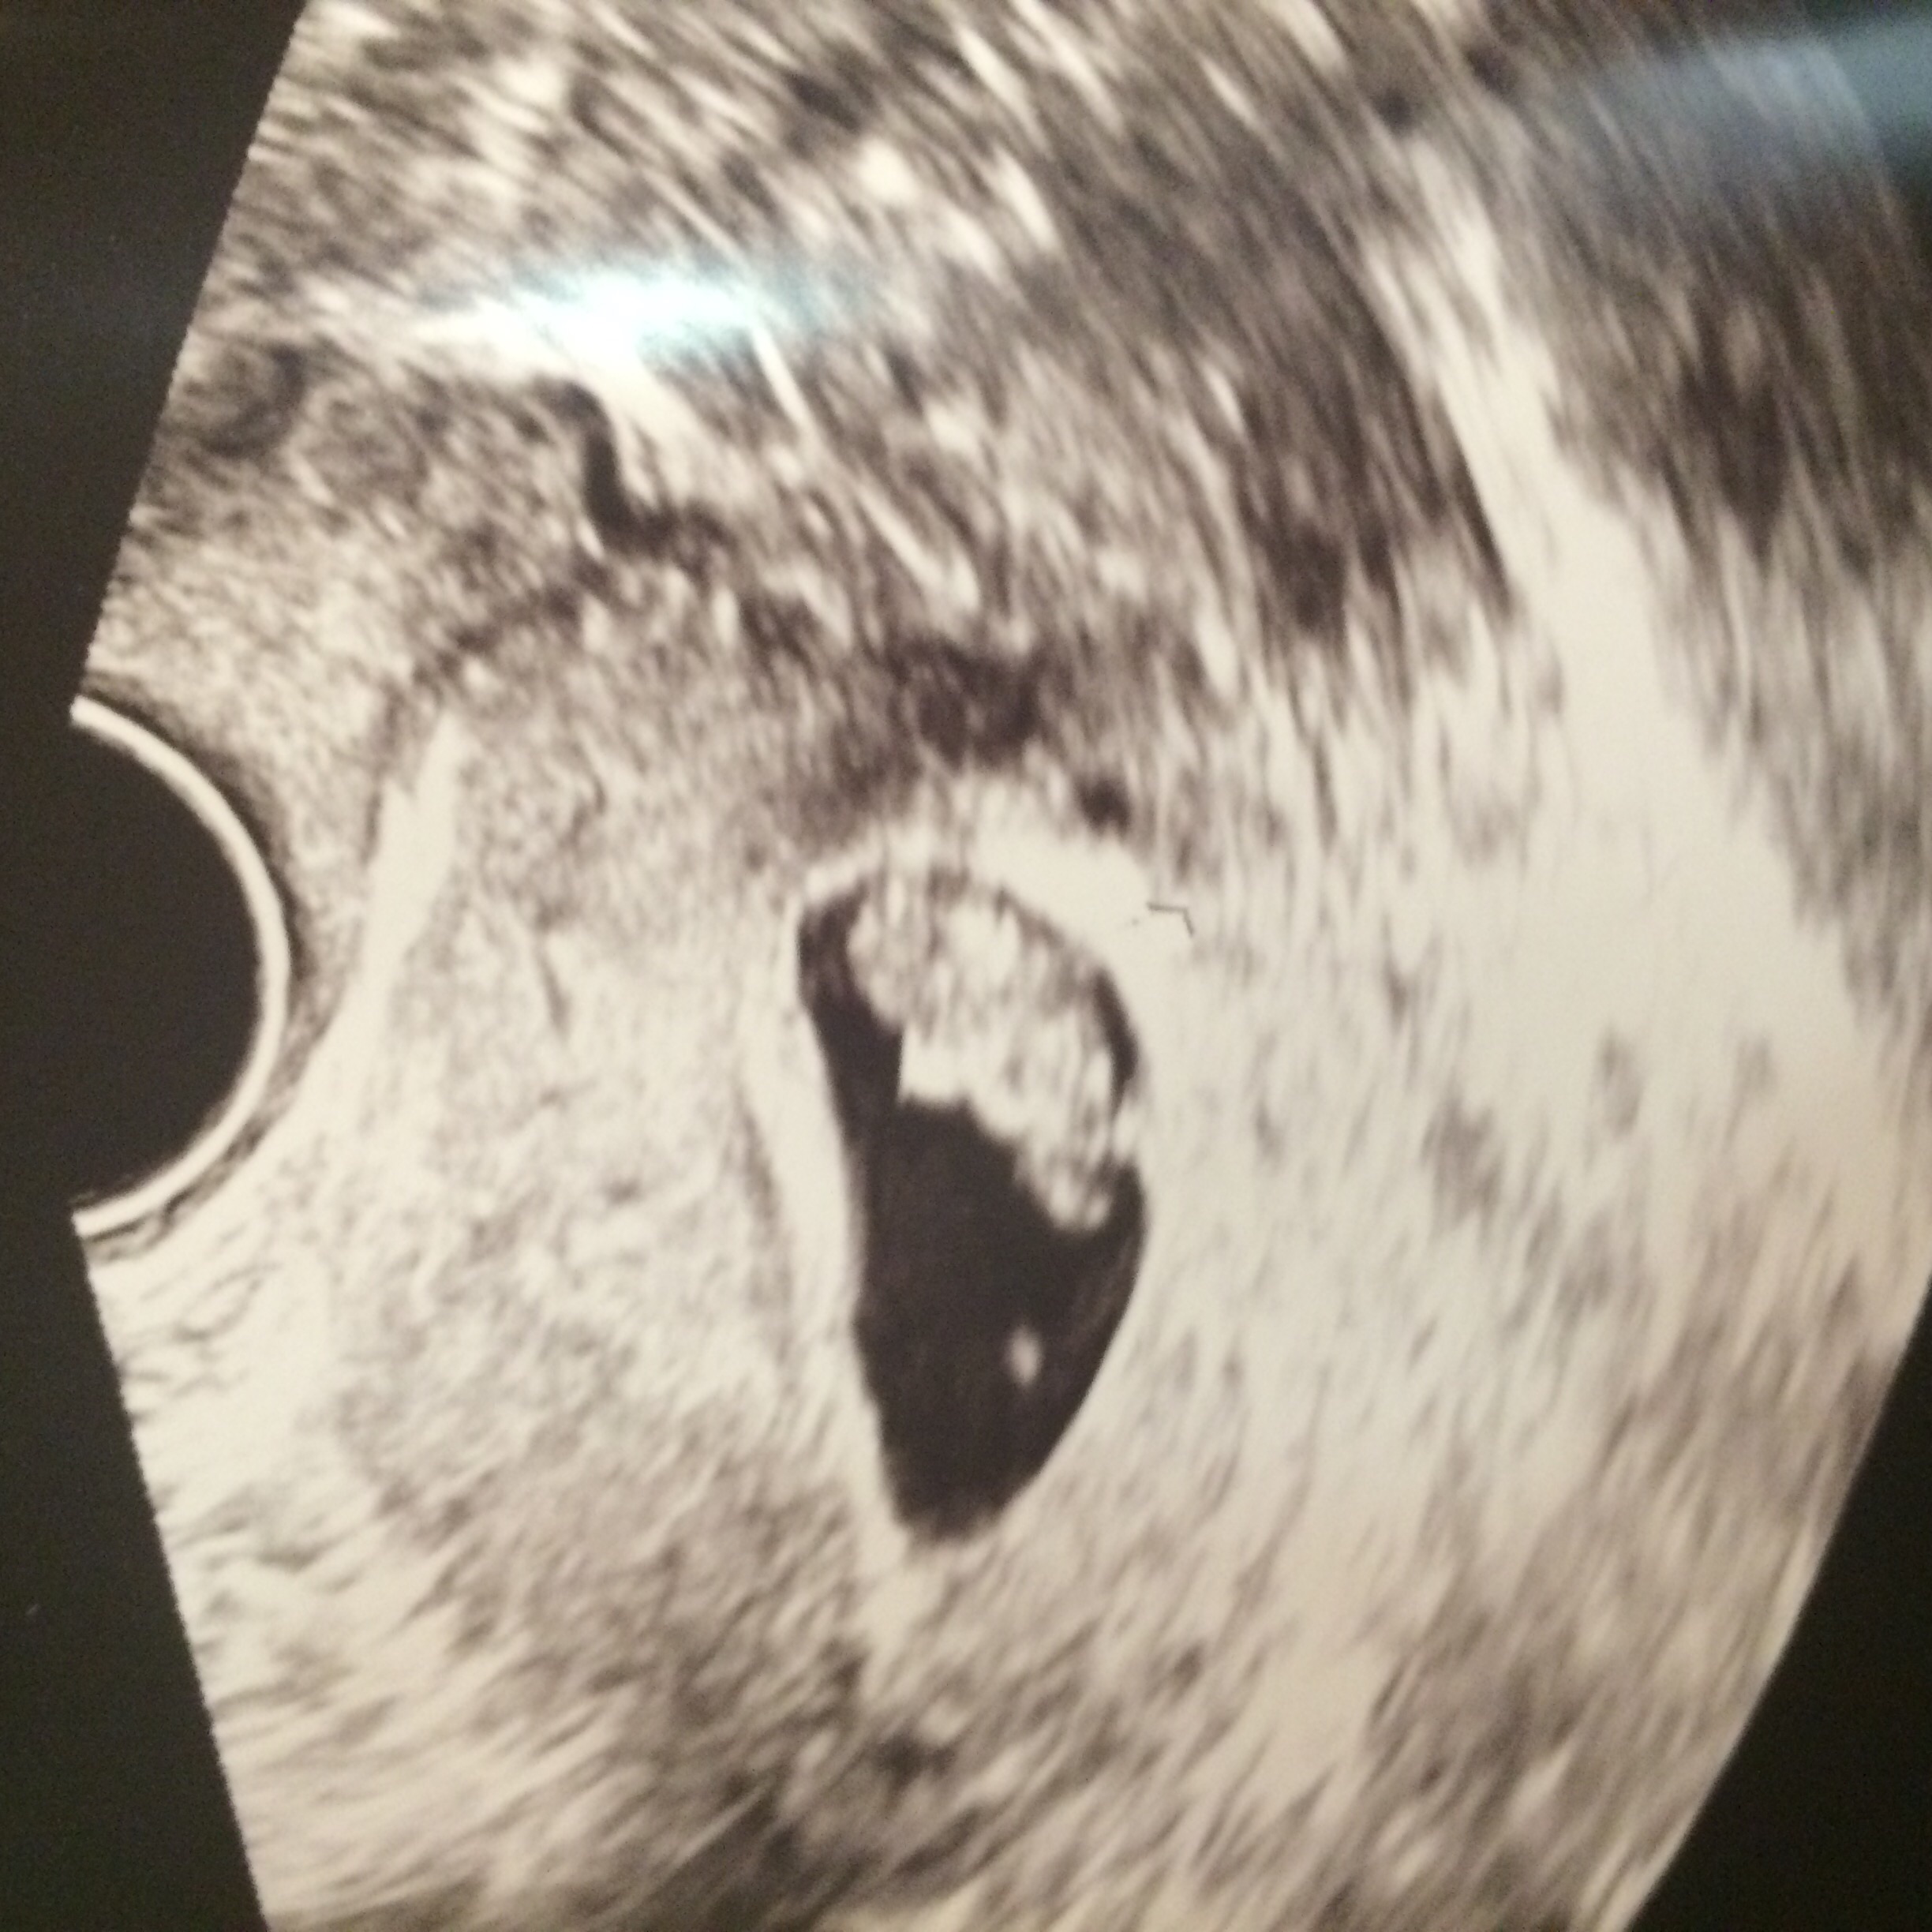

• I woke up early 1 morning with severe pain, hot & sweaty so we saw the obstetrician that day. He did a vaginal ultrasound as the tummy 1 didn't reveal much & I played doctor to him, pointing out the sack, yolk & then we saw the flicker of a heart beat :-) One of the best moments of my life! We hadn't done the dating scan before then & I asked for his opinion on how far along & he said just shy of 6 weeks - that was last Tuesday & our dating scan is next Wednesday :-)